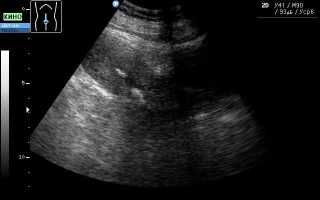

Эти образования хорошо визуализируются при проведении ультразвукового исследования или магнитно-резонансной томографии. Однако во время УЗИ невозможно увидеть ткани, из которых состоит образование, поэтому можно лишь предполагать наличие кальцината. Такая ситуация требует дополнительного обследования женщины, чтобы исключить более серьезные заболевания, чем просто наличие отложений солей кальция.

Одним из наиболее распространенных методов диагностики является ультразвуковое исследование репродуктивных органов. Гинекологи часто рекомендуют трансабдоминальное УЗИ, которое позволяет выявлять патологии органов с помощью датчиков, перемещаемых по животу пациентки.

- трехмерное УЗИ – современный метод диагностики заболеваний матки, который позволяет визуализировать кальцинаты в трехмерном формате;

На сегодняшний день трехмерное УЗИ считается самым точным методом диагностики заболеваний матки, однако его стоимость значительно выше по сравнению с другими методами.